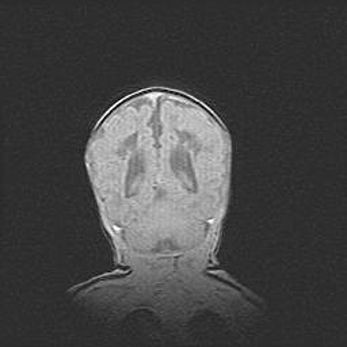

Открытая гидроцефалия.

Возраст: 9 месяцев 12 дней

Вес: 6800 г

Пол: мужской

Окружность головы: 41,5 см

Срок гестации: 28 недель

Гидроцефалия головного мозга у новорожденных имеет характерный признак: опережающий рост окружности головы приводит к визуально хорошо определяемой гидроцефальной форме сильно увеличенного в объёме черепа. Детские неврологи определяют следующие симптомы гидроцефалии у грудничков: выбухающий напряжённый родничок, частое запрокидывание головы, смещение глазных яблок к низу.